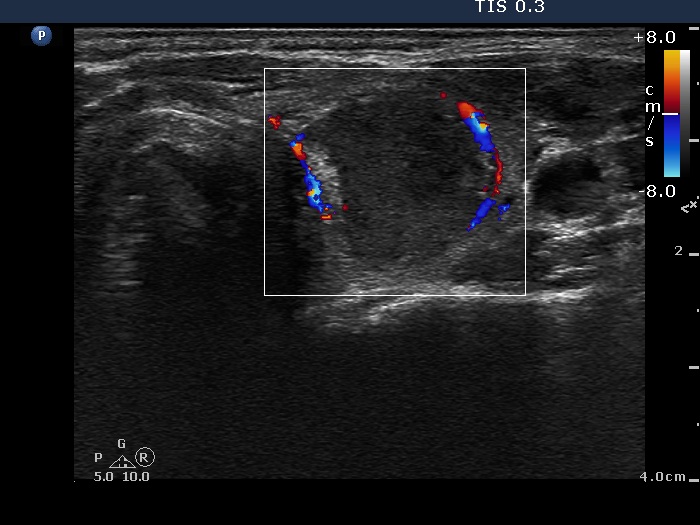

Six weeks after the therapy (ultrasonographic picture 3)

Right lobe, horizontal scan, color Doppler mode. In contrast with the previous occasions, the nodule clearly presents a type 2 vascular pattern.